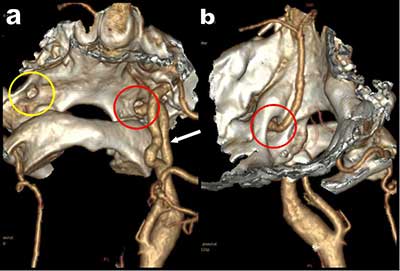

Figure 2

3D volume rendering views with bone structures showing the hypoglossal artery penetrating the skull through the supracondylar hypoglossal fossa.